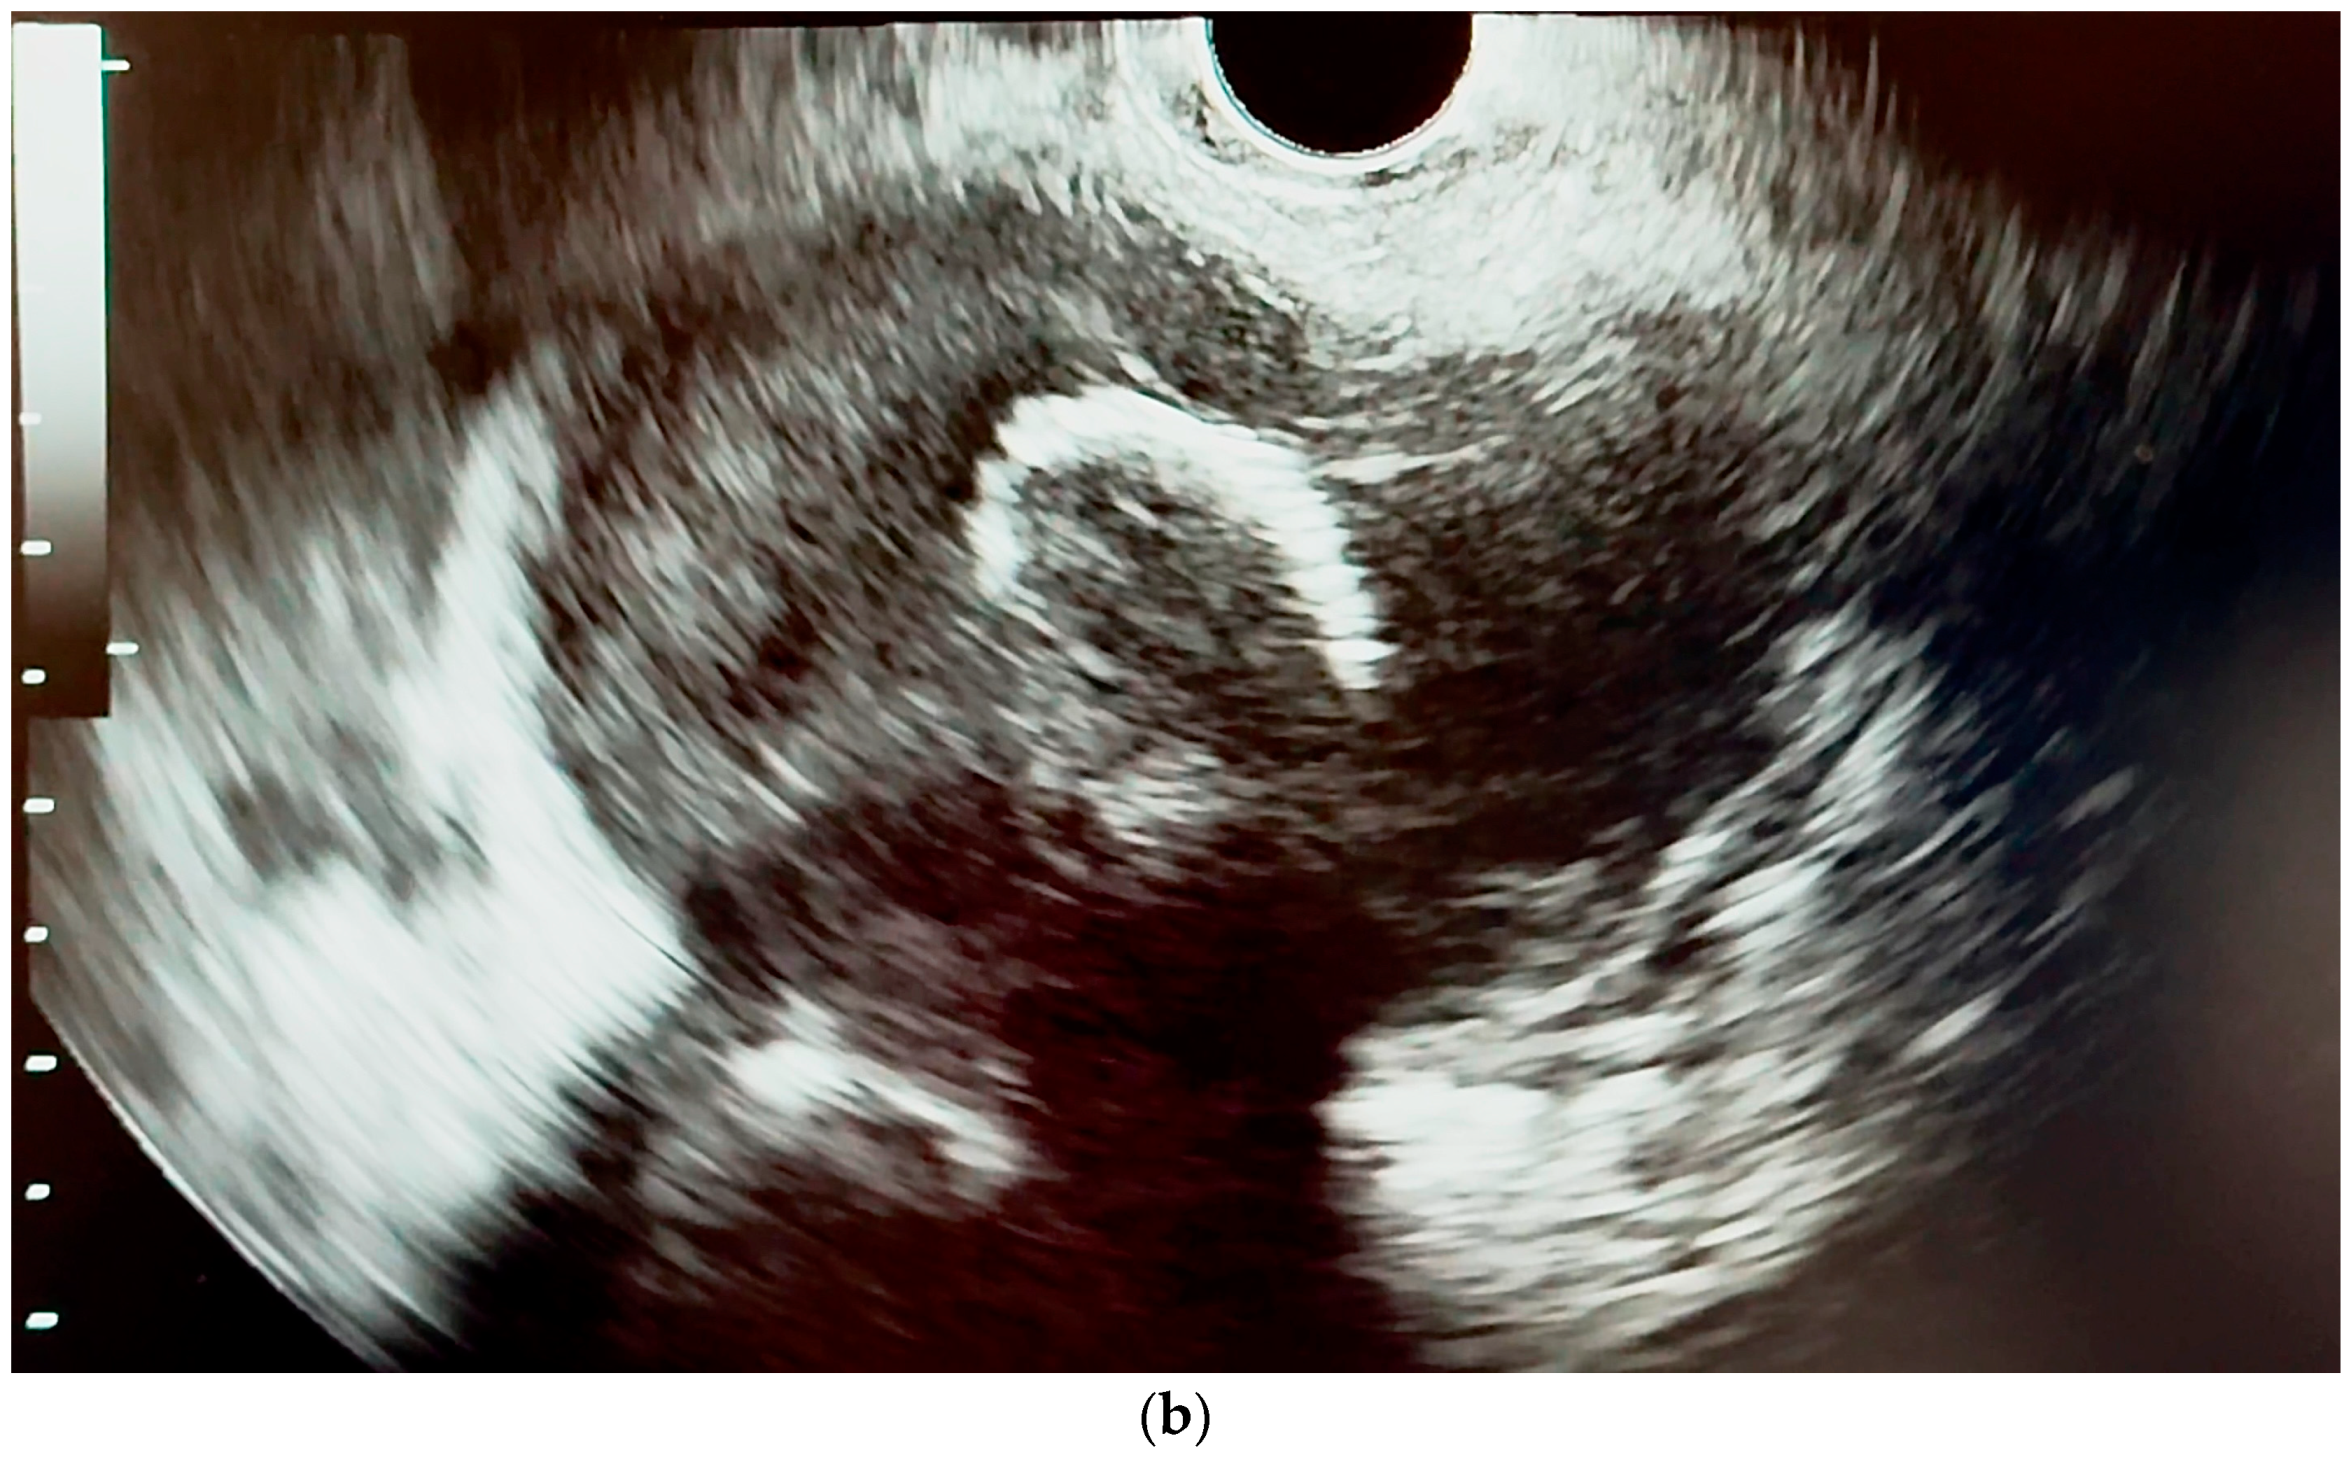

6.4.1. Endoscopic Ultrasound (EUS)

- Orzan, R.I.; Pojoga, C.; Agoston, R.; Seicean, R.; Seicean, A. Endoscopic Ultrasound in the Diagnosis of Extrahepatic Cholangiocarcinoma: What Do We Know in 2023? Diagnostics 2023, 13, 1023. [Google Scholar] [CrossRef] [PubMed]

- Otsuka, Y.; Kamata, K.; Hyodo, T.; Chikugo, T.; Hara, A.; Tanaka, H.; Yoshikawa, T.; Ishikawa, R.; Okamoto, A.; Yamazaki, T.; et al. Utility of contrast-enhanced harmonic endoscopic ultrasonography for T-staging of patients with extrahepatic bile duct cancer. Surg. Endosc. 2022, 36, 3254–3260. [Google Scholar] [CrossRef] [PubMed]